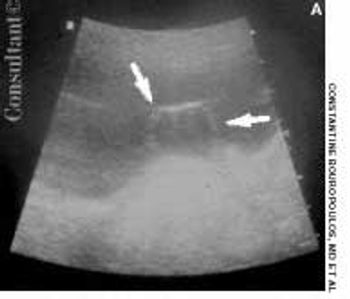

A 67-year-old woman was admitted to the hospital with fever, chills, unilateral flank pain, dysuria, and urinary frequency and urgency. Her past medical history included several febrile relapses of infection.